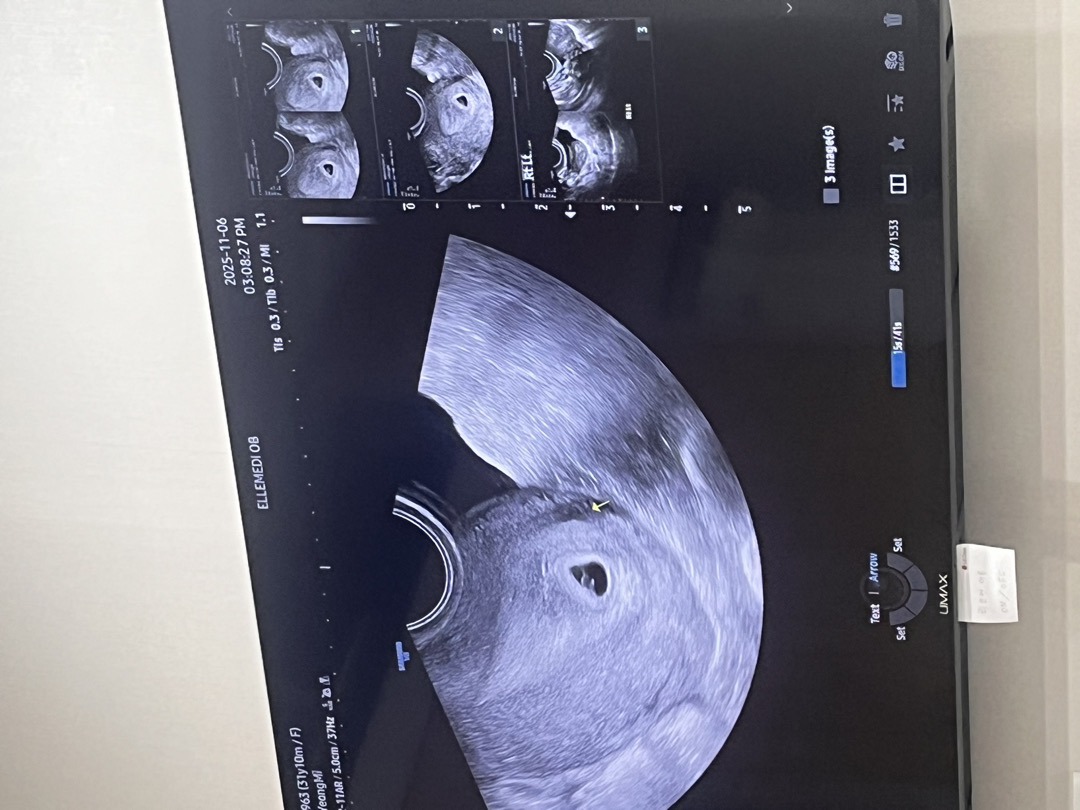

안녕하세요 임신 6주 1일차 산모입니다 요즘 아랫배가 너무 당기네요 시도때도 없이요.. 왜 그런걸까요? 무서워요 저번주 초음파에서 아기집도 잘 생기고 난황도 잘 보였어요 근데 저번주보다 배가 넘 땡겨요 다른 분들도 그러신가요?

6주5일차인데 저도 아랫배가 생리통하듯이 조금 뻐근한게 계속 있어요~ 걱정했는데 오늘 건강한 심장소리 듣고 왔어요☺️ 엄마 쫌만 더 파이팅 !